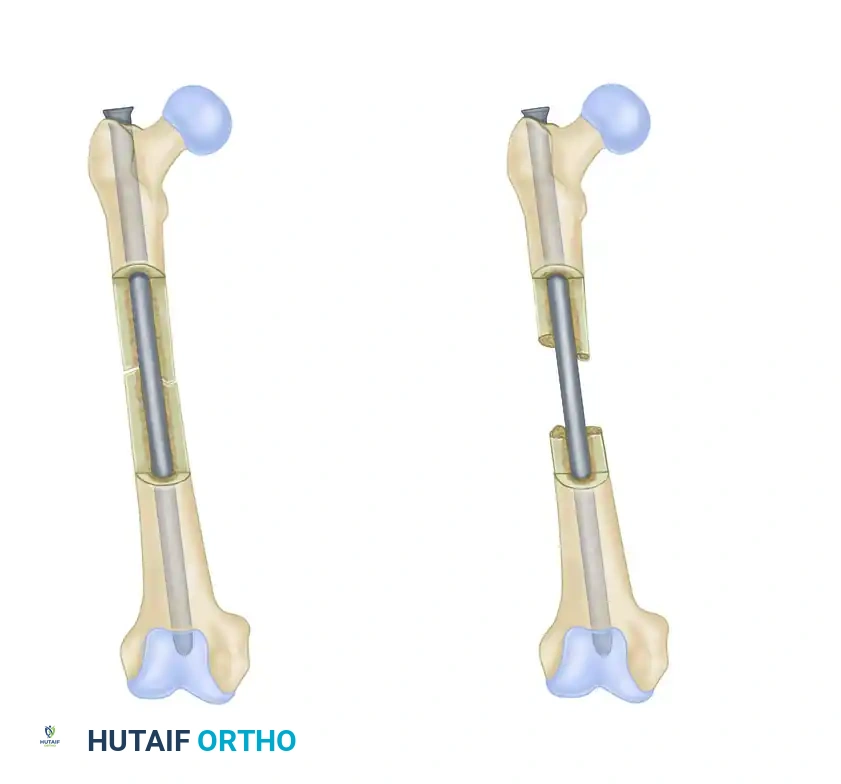

FIGURE 53-36: Dynamic (A) and static (B) locking of an intramedullary nail. Dynamic locking allows for controlled axial compression, whereas static locking rigidly controls both length and rotation.

- Static Locking: Involves placing screws in round holes at both the proximal and distal ends of the nail. This configuration locks the bone to the nail entirely, preventing any axial shortening or rotational movement. It is mandatory for comminuted, spiral, or bone-loss fractures where maintenance of limb length is critical.

- Dynamic Locking: Involves placing a screw through a slotted hole at one end of the nail, allowing the bone fragment to slide axially along the nail while still preventing rotation. This allows contact-compression forces to impact the fracture surfaces during weight-bearing—a highly desirable physiological stimulus for bone union. Dynamization can be performed as a secondary procedure (removing static screws to allow a slotted screw to slide) if delayed union is observed.

In highly comminuted fractures, static locking with multiple distal and proximal screws is essential to maintain length and prevent rotational collapse during the early phases of healing.